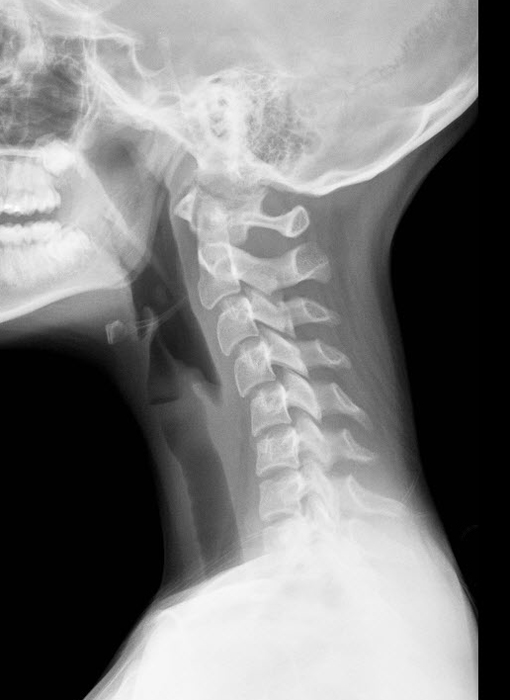

This is how your neck is supposed to look- a nice “C” curve: